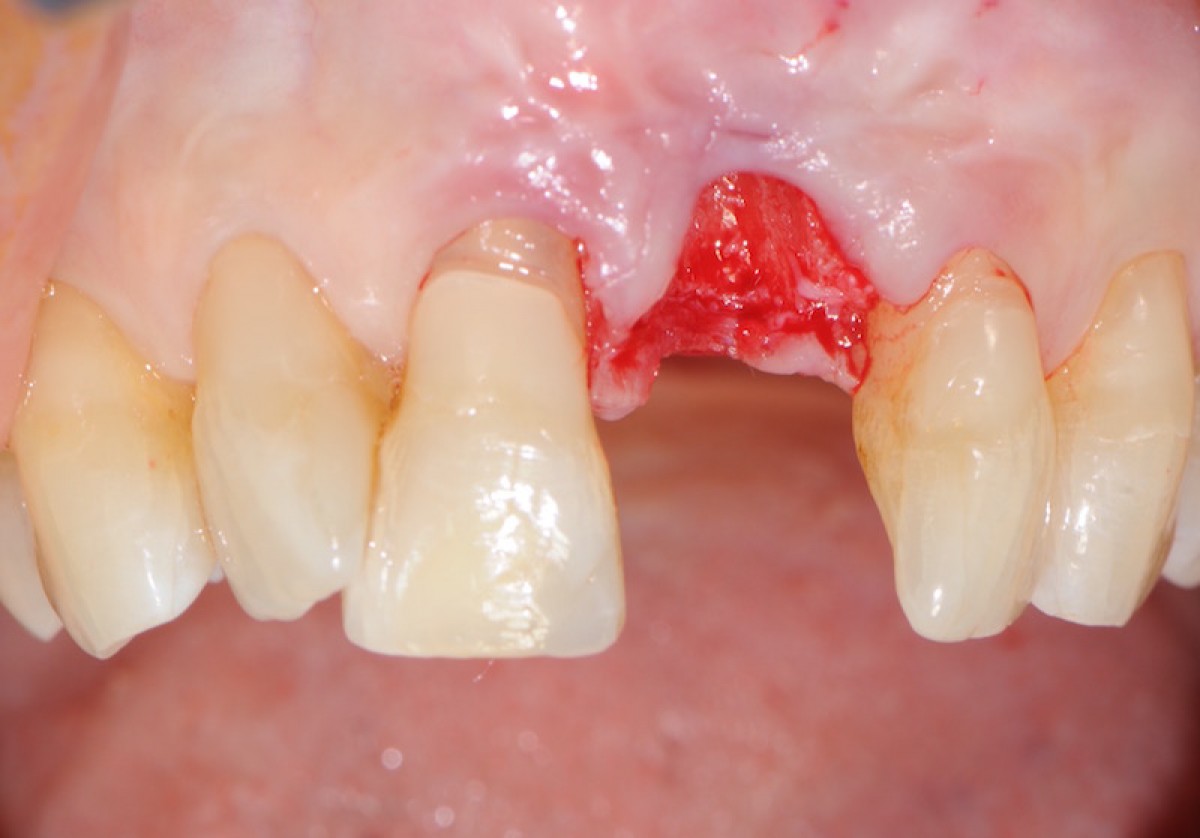

The objective of this prospective cohort study is to test the performance of a new xenogenic collagen matrix as a socket sealing material, to allow second-intention healing of post-extractive sockets filled with a xenogenic bone substitute or with an immediate submerged implant.

10 patients were recruited, presenting a single-rooted tooth scheduled for extraction. After atraumatic tooth removal, the post-extractive alveolus received either a socket preservation procedure or an immediate submerged implant. In both cases, the gingival margins of the alveolus were sealed with a xenogenic collagen matrix (Mucoderm, Botiss Dental, Zossen, Germany). The following parameters were evaluated:

• 8 weeks after surgery, full wound closure was achieved in 9 out of 10 sites with healthy keratinized tissue;

• the histological evaluation of gingiva sample revealed the presence of healthy keratinized gingival tissue, with no signs of aberrations or anomalies;

Preliminary results from this study suggest that this new xenogenic porcine-derived collagen matrix could represent a valuable alternative to allow second intention healing of post-extractive sockets filled with a xenogenic bone substitute or with an immediate submerged implant. New randomized clinical trials are needed to confirm the preliminary results obtained in the study and evaluate the long-term benefits.